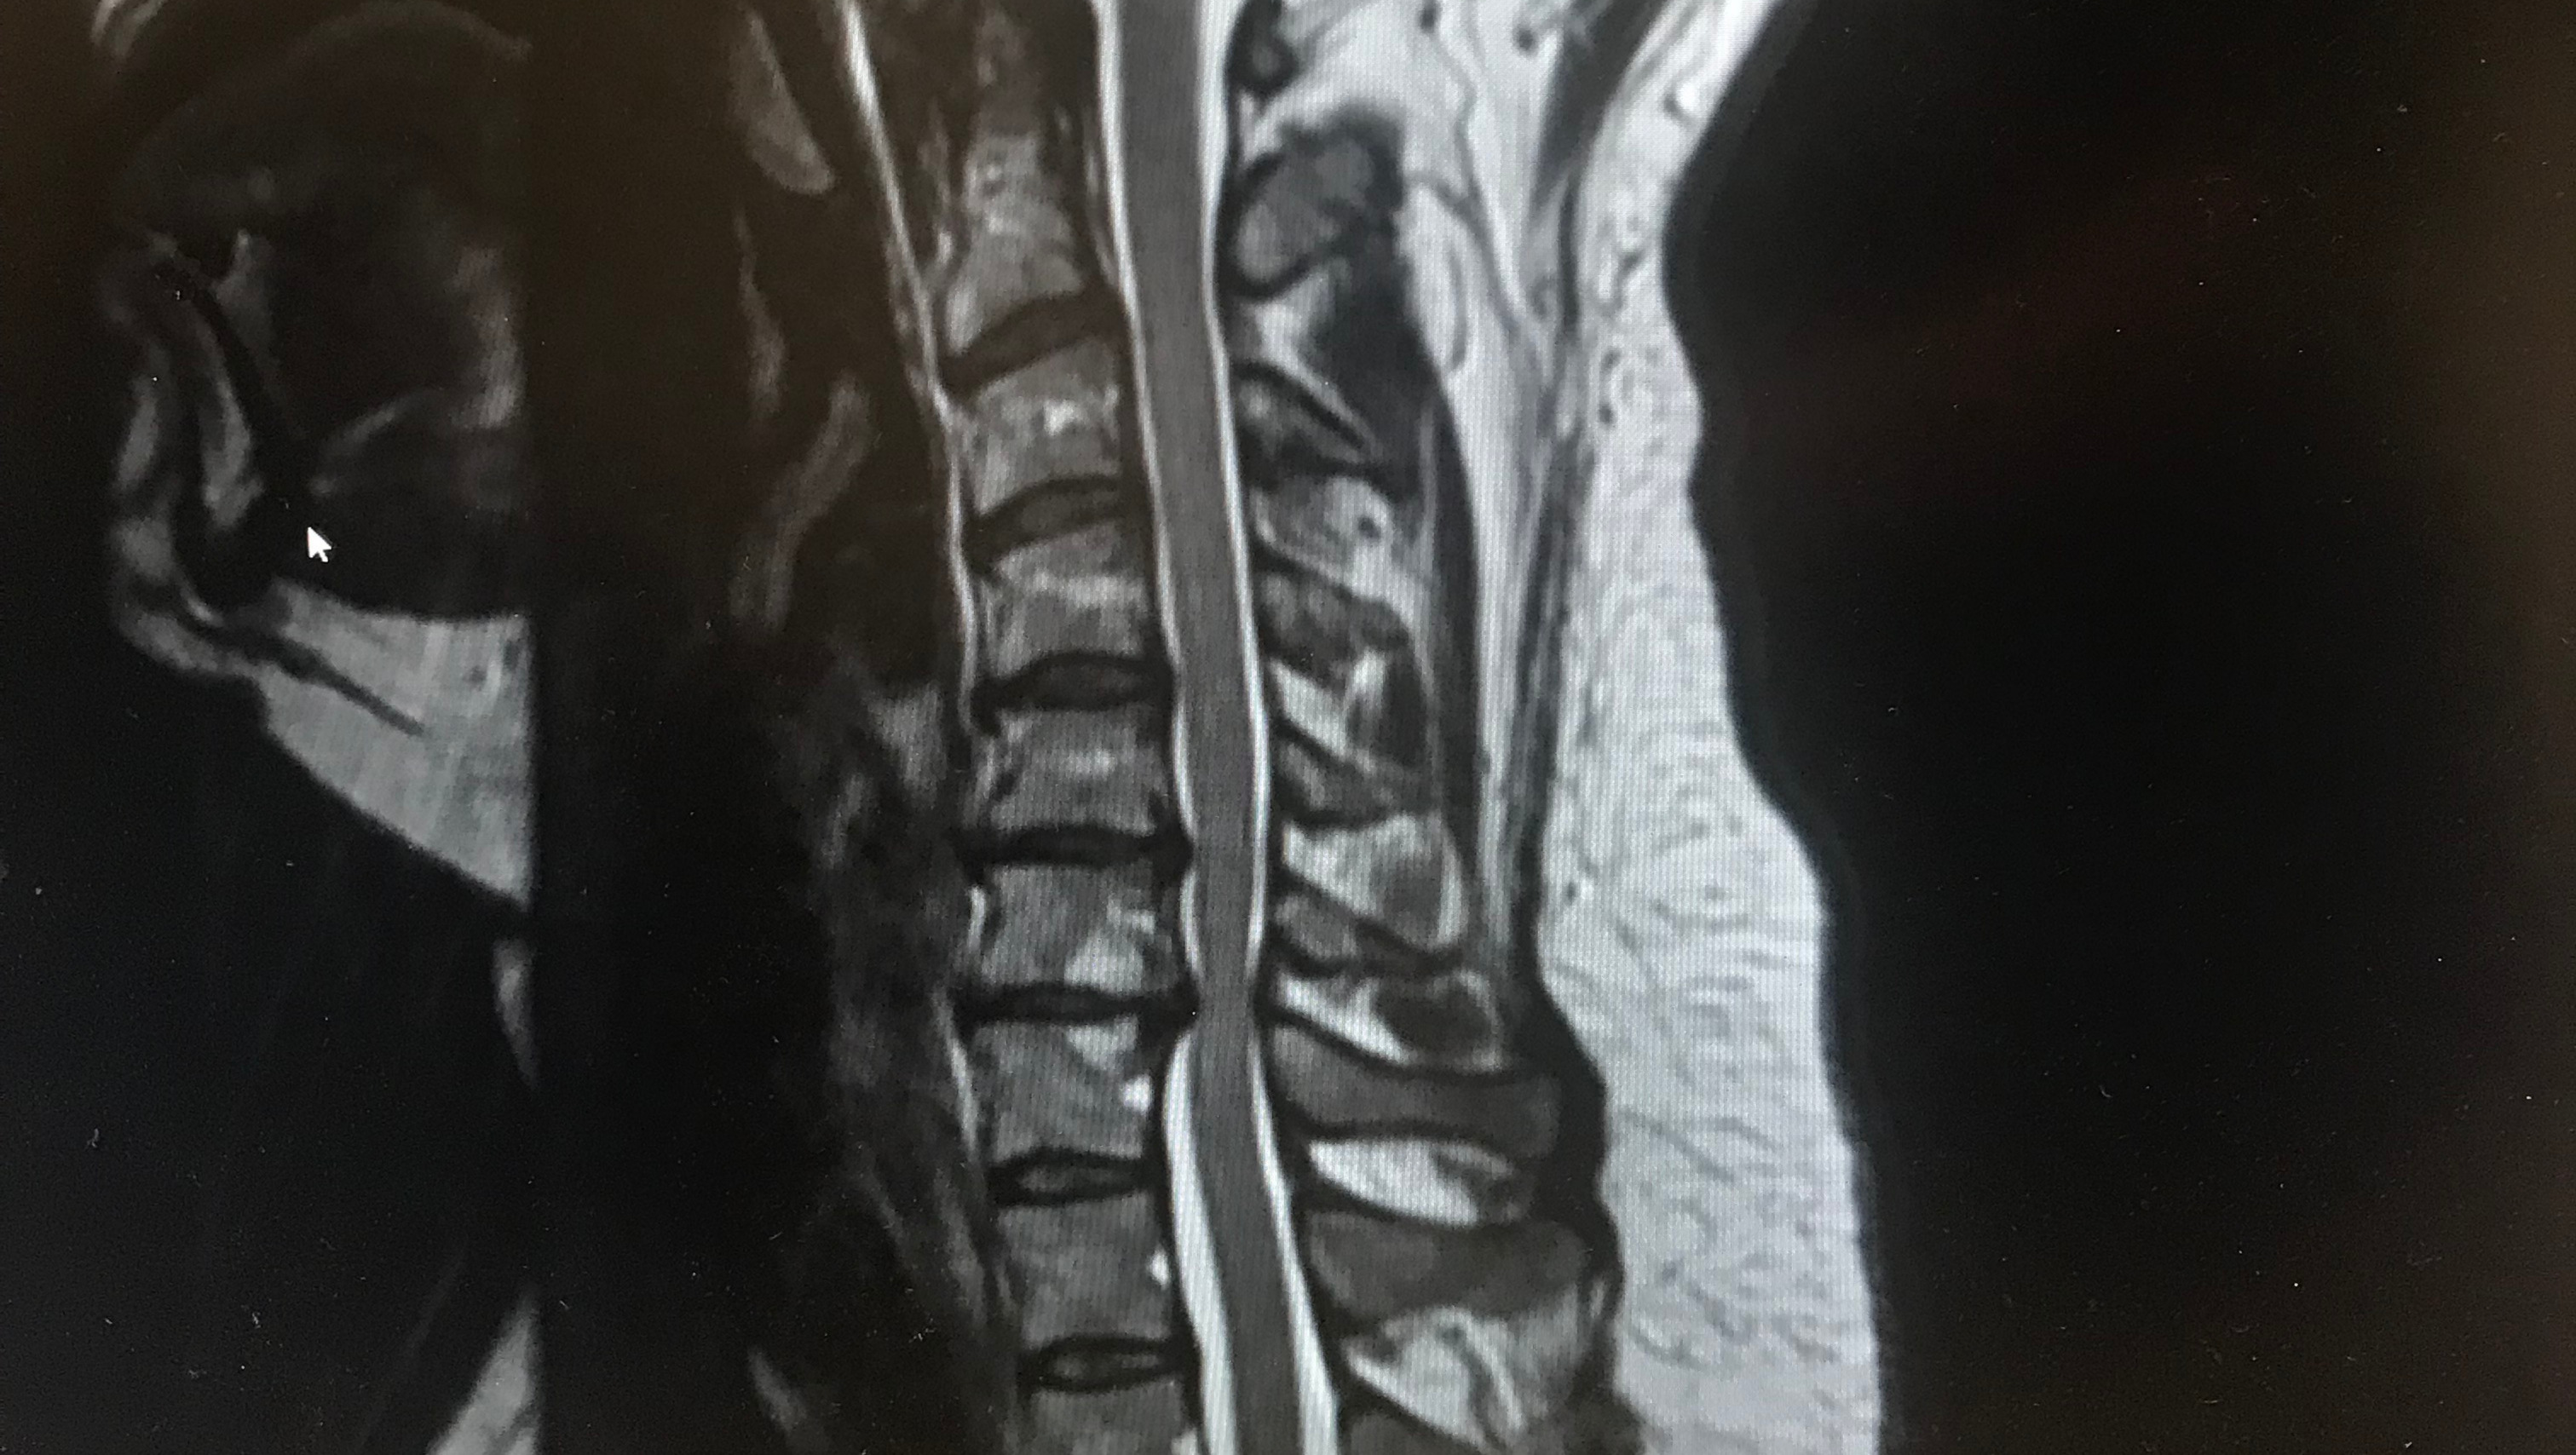

Back in August 2019, my wife Keri had surgery to put a metal plate and bone grafts in her neck to try to prevent further damage to her body as the discs had deteriorated in her neck. The doctor said that the surgery wouldn't fix the problem but prevent further damage. She was diagnosed with Spinal Stenosis Of Cervical Spine With Myelopathy. I started a GoFundMe back then to help her get by after surgery through her recovery.

A few months ago she was seen by a Neuro-Surgeon and when he did a MRI he found that her spinal cord is being compressed by her C5/C6/C7 vertebrae. The diagnosis is "Spinal Stenosis Of Cervical Spine With Myelopathy." They have to go in and insert bone grafts in between the vertebrae and screw her vertebrae together with a metal plate. The recovery time is 4-6 weeks, before physical therapy.

Below is a photo of the damage.>>